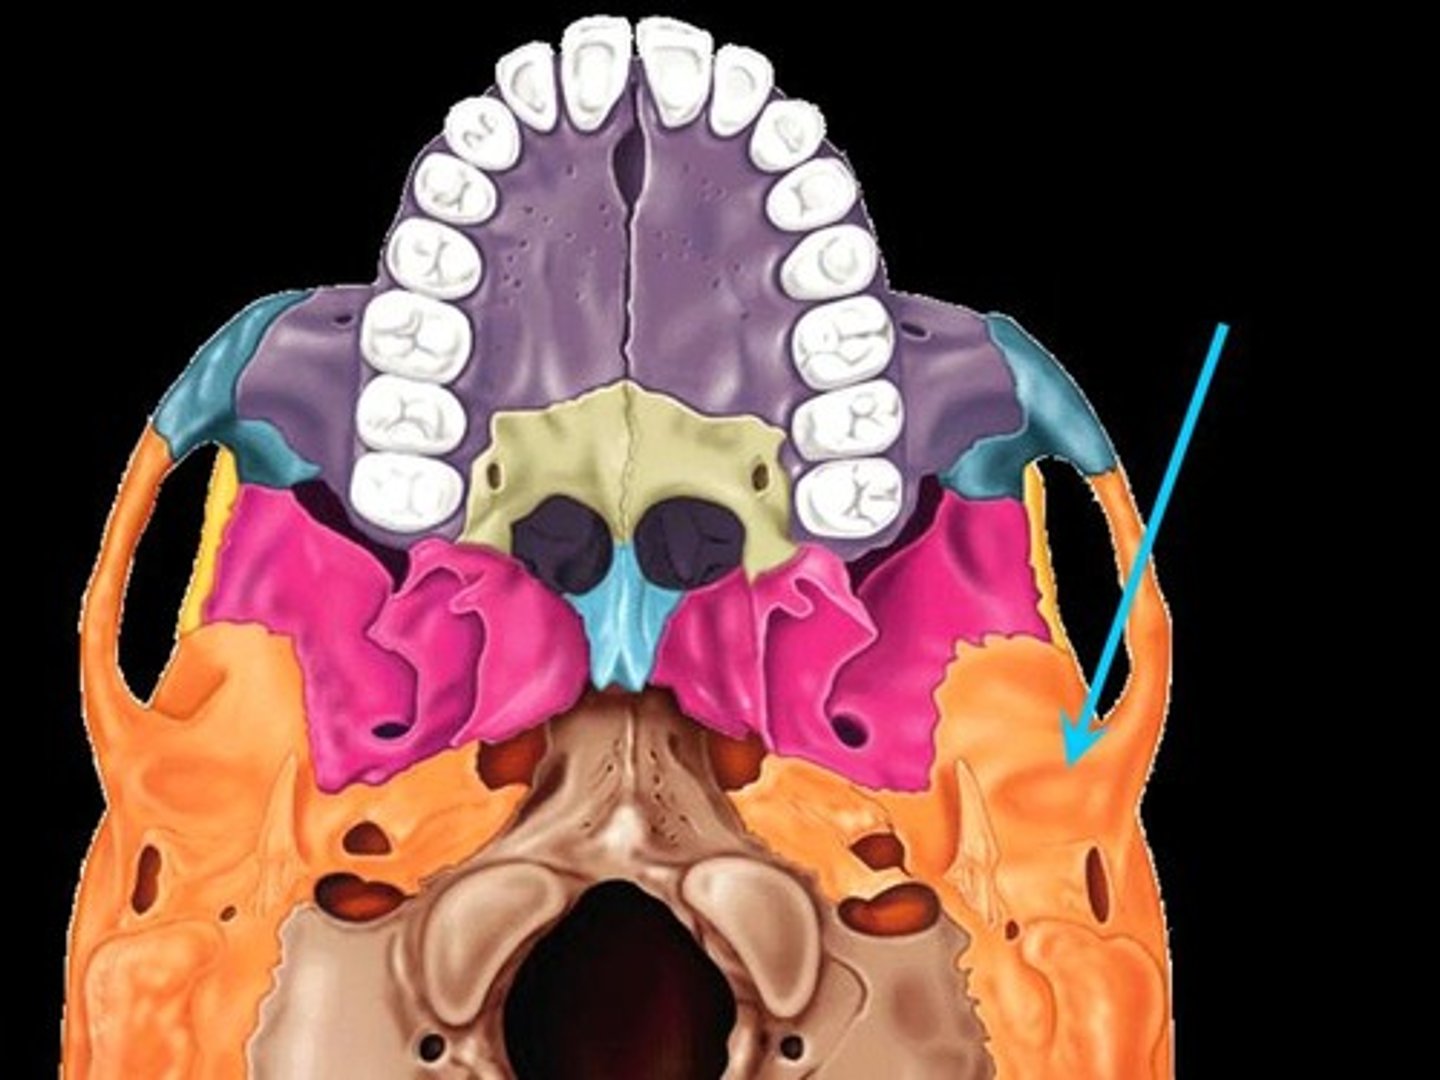

Styloid Process

Pole-like process extending downward from the temporal bone on each side of the skull

Stylomastoid Process

Carotid Canal

The passageway in the temporal bone through which the internal carotid artery enters the middle cranial fossa from the neck

Mandibular Fossa

The depression in the temporal bone into which the condyle of the mandible fits